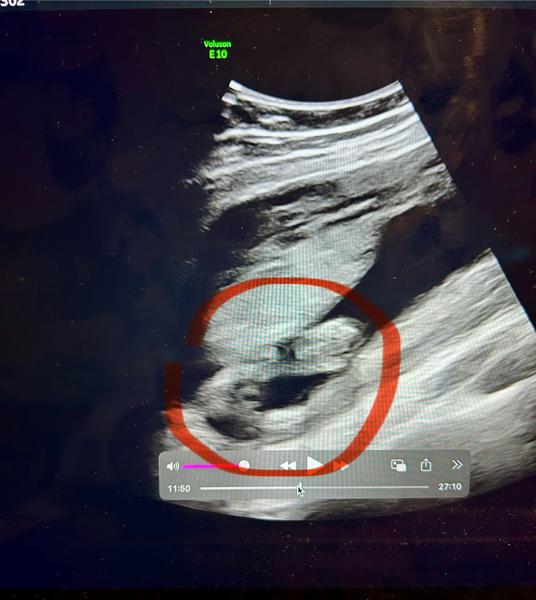

doktor mi stále nepotvrdil pohlaví. I já na jedné fotce vidím holku, na druhé kluka. Co myslíte? :D

@lenca554 já bych spíš řekla holka. Ale nejsem odborník, jen máma dvou holek 🙂 takže bych počkala na potvrzení od dr.